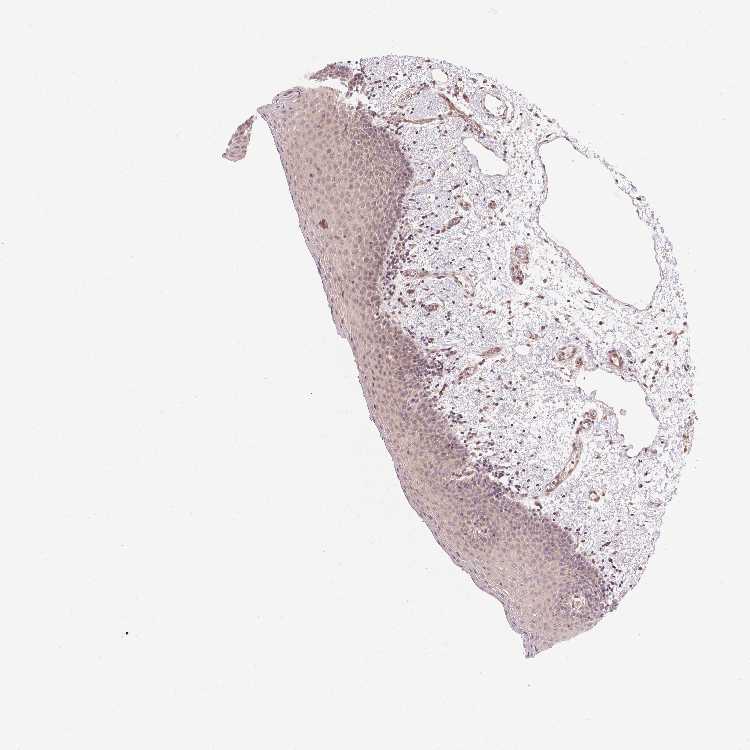

TISSUE PRIMARY DATA ORAL MUCOSA Show tissue menu

ORAL MUCOSA - Antibody stainingi

Antibody staining in the annotated cell types in the current human tissue is reported as not detected, low, medium, or high, based on conventional immunohistochemistry profiling in selected tissues. This score is based on the combination of the staining intensity and fraction of stained cells.

Each image is clickable and will lead to virtual microscopy that enables deeper exploration of all samples and also displays staining intensity scores, fraction scores and subcellular localization as well as patient and tissue information for each sample.

Antibody HPA050215

Squamous epithelial cells Not detected